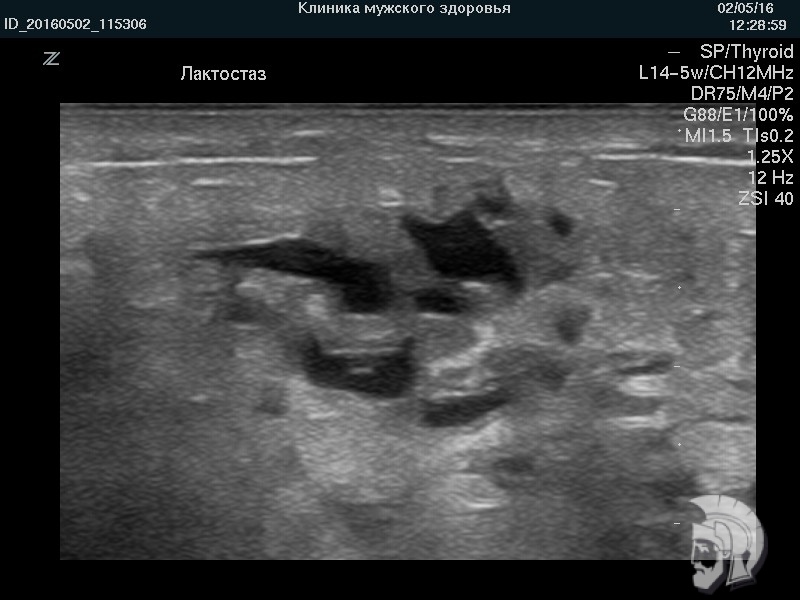

| УЗИ груди. Фото ЛАКТОСТАЗа. Определяются многочисленные расширенные протоки в виде линейных и причудливой формы «темных» структур |

Фото лактостаза в режиме 3D. Тот же случай.

Расширенные и заполненные молоком млечные ходы указаны стрелками.

Мужчина ВОВРЕМЯ привел жену. Грудь сохранили БЕЗ ОПЕРАЦИИ |